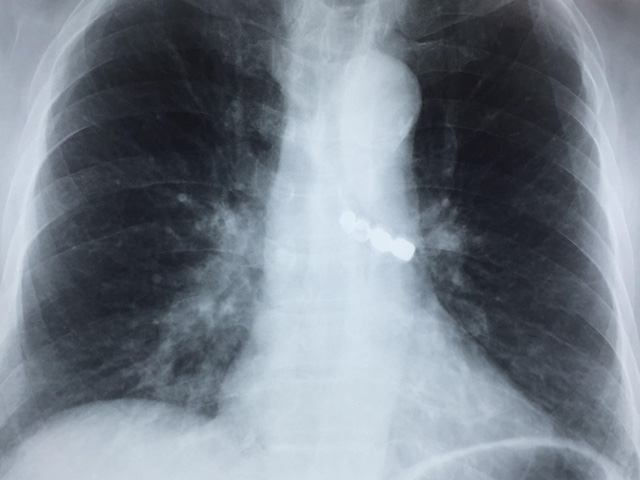

Cụ ông này đã được nội soi dạ dày tại Bệnh viện đa khoa tỉnh Thái Bình để tìm dị vật nhưng không thấy; được chụp phim X-quang phổi và phát hiện ra dị vật trong đường thở. Do vượt quá khả năng can thiệp nên người bệnh được chuyển cấp cứu lên Bệnh viện Phổi Trung ương.

4 chiếc răng giả bị rơi trong phế quản của cụ ông.